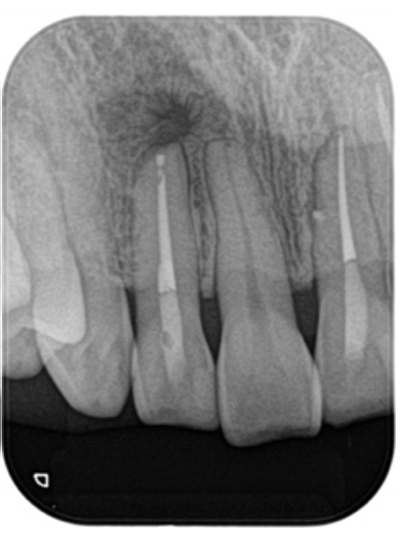

術前、右上2に大きな透過像(黄色矢印、炎症の黒い影)と左上1にも透過像(赤矢印)が見られます。腫れの原因は、歯髄壊死と根尖性歯周炎と診断し、まずは根管治療を行いました。左上1の根尖も透過像(緑矢印)がありましたが、歯髄の反応は正常でしたので歯髄壊死とは診断せず治療は行いません。

• 根管治療後4ヶ月、左上1の透過像(赤矢印、黒い影)は小さくなり治癒傾向が確認できますが、右上2(赤矢印)は以前より広がってきていて、腫脹の再発がありました。非治癒判定となり、次の治療法として歯根端切除術を行うこととなりました。歯根端切除術を行わない医院ではこの時点で抜歯が宣告されてしまうでしょう。

• 術前レントゲン画像

• 歯根端切除術後1年のレントゲン画像